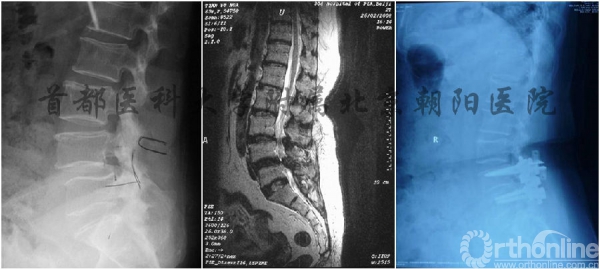

生物力从理论上证实Coflex在Topping-off技术中应用的有效性,北京朝阳医院海涌主任团队进一步对临床应用进行了评估,两年以上随访研究结果显示Topping-off手术的近中期疗效较为满意,手术对于腰椎矢状面平衡有一定保护作用。相邻节段无退变发生,并且未发现术后临床疗效与矢状面平衡指标存在明显相关性,该结果在2014年《脊柱外科杂志》和2015年《中国脊柱脊髓杂志》上发表。

双节段腰椎管狭窄患者给予Topping-off手术